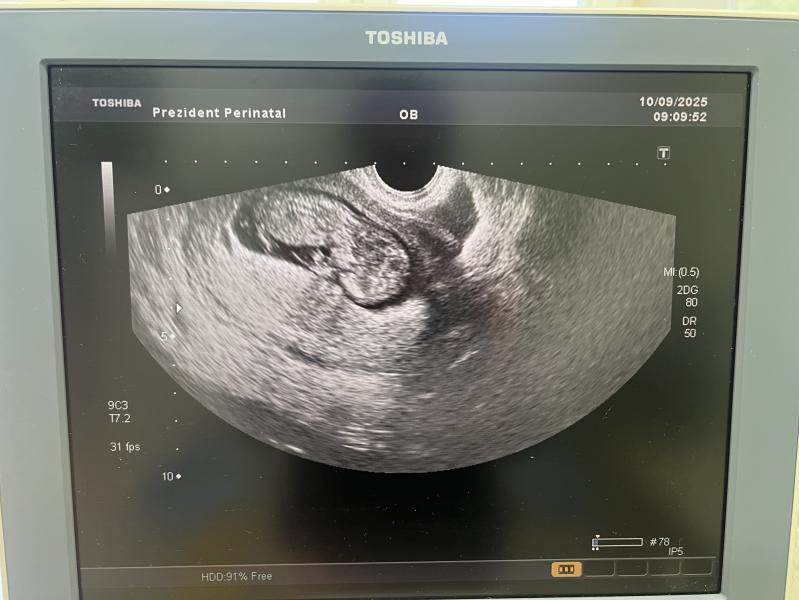

1 скрининг. Вышла с кабинета узи , руки трясутся . Узист намерила твп около 5 (норма до 3). Начала звать другую узистку более опытную , потом перемерила сама твп-2.1 (по мне конечно тоже высоковато , но с 1 ребенком было так же ). Сказала все хорошо. А у меня осадок остался может она ошиблась во второй раз . Записалась я на скрининг платно. Поеду тому кому доверяю . Как говорится : ложки нашлись , но сомнения остались .